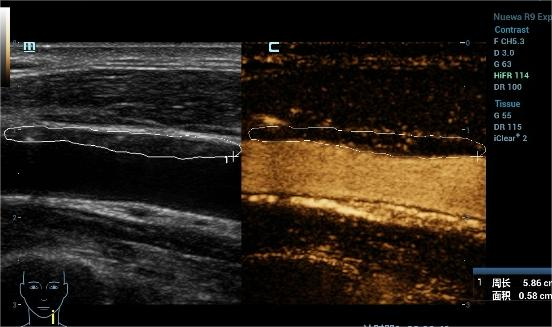

05颈动脉的超声造影报告怎么看?

我们把颈动脉斑块造影分做4级:I~IV级依此显示新生血管从无到有,逐步增多。其中I~II级为稳定斑块,II~IV级为易损斑块。我们可以借助超声造影清晰地显示斑块的表面溃疡,整体形态等结构; 还能清晰显示动脉管腔狭窄的位置以及是否合并闭塞,指导临床进一步干预及评估干预效果。